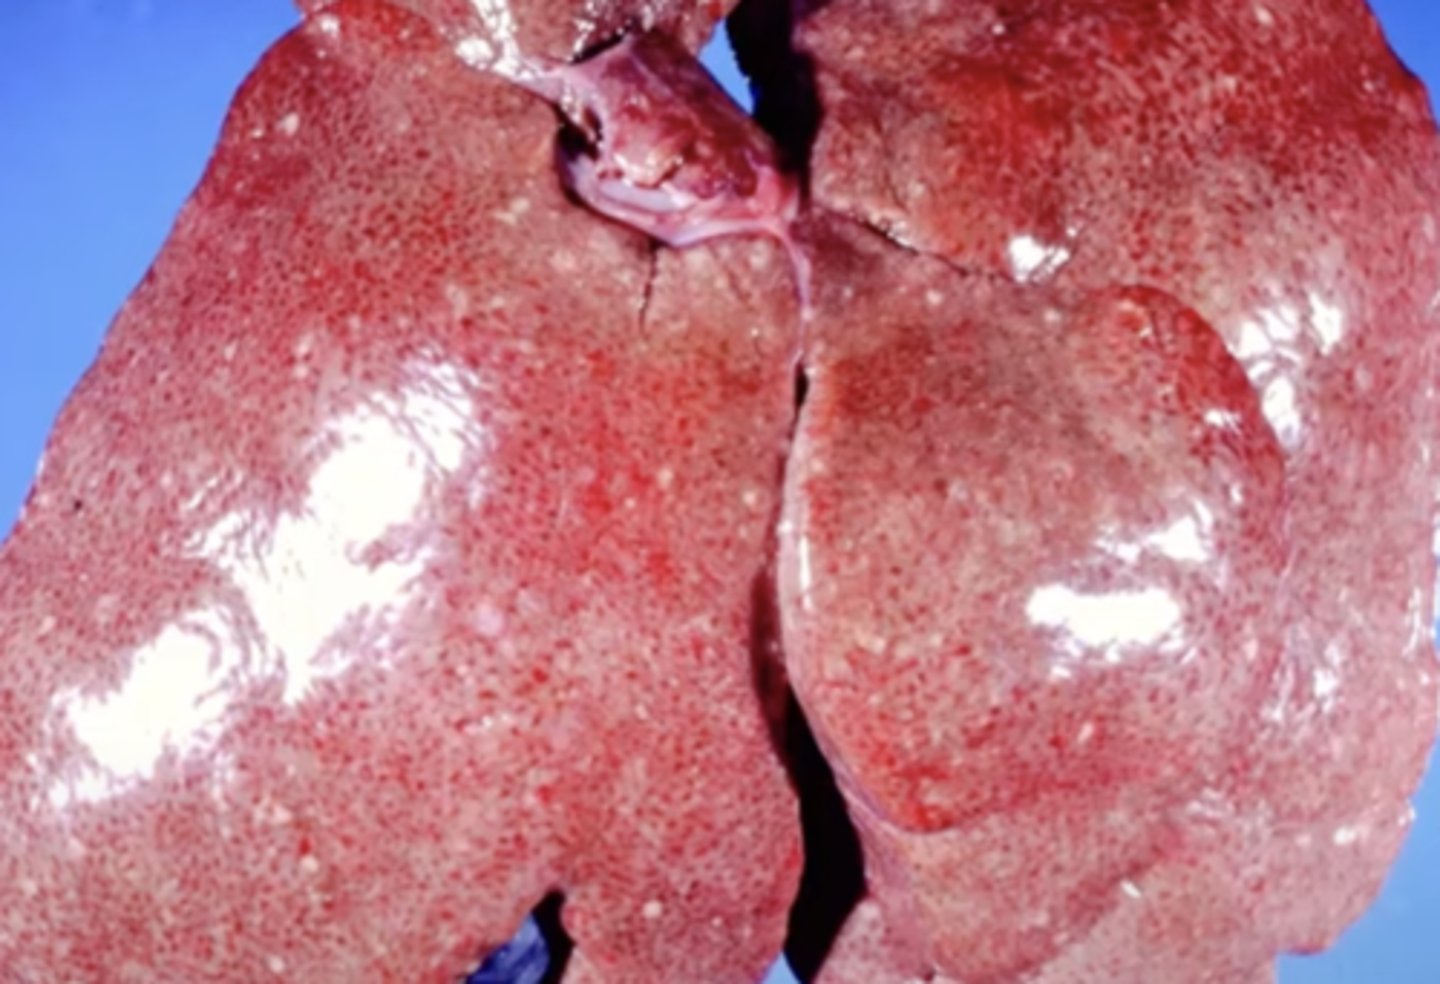

Cholangiocarcinoma

-tumor of the bile ducts

What has caused this gross appearance of this liver?